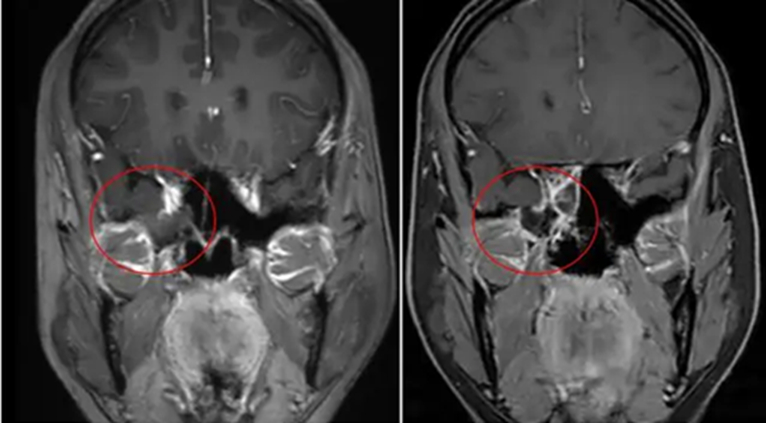

Tại khoa Tai Mũi Họng - Phẫu thuật đầu cổ, bác sĩ nhận định các triệu chứng của chị rất điển hình cho tình trạng rò dịch não tủy. Kết quả chụp CT và MRI sọ não cho thấy thành ngoài xoang bướm bên phải của bệnh nhân bị khuyết xương, một phần mô não thoát vị qua lỗ khuyết, kèm theo dịch não tủy rò rỉ. Ngoài ra, chị còn mắc tình trạng dịch não tủy chèn ép tuyến yên và tăng áp lực nội sọ lành tính.

Các bác sĩ đã tiến hành phẫu thuật nội soi qua đường mũi, nhờ đó có thể tiếp cận trực tiếp vùng tổn thương ở nền sọ, xử lý phần mô thoát vị và dùng mô tự thân như mỡ, cân để vá kín lỗ rò theo nhiều lớp, đồng thời tránh được các cấu trúc quan trọng như động mạch cảnh và xoang hang.

Sau phẫu thuật, kết quả kiểm tra cho thấy vùng tổn thương đã được phục hồi tốt, không còn dịch rò, các triệu chứng chảy nước mũi biến mất hoàn toàn. Bệnh nhân hồi phục và xuất viện, trở lại sinh hoạt bình thường.